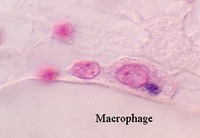

Connective Tissue

- Specialized cells in connective tissue

- Monocytes